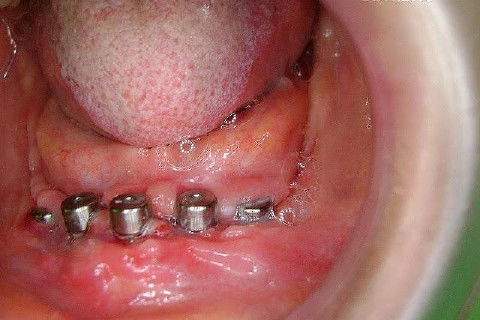

Protocolo Inferior com 5 Implantes - Parte I - Planejamento + Cirurgia

Apesar da boa adaptação e estética satisfatória, a principal queixa da paciente era a instabilidade da prótese inferior, como sempre ocorre nestes casos...atrofia do rebordo alveolar e perda da função mastigatória.